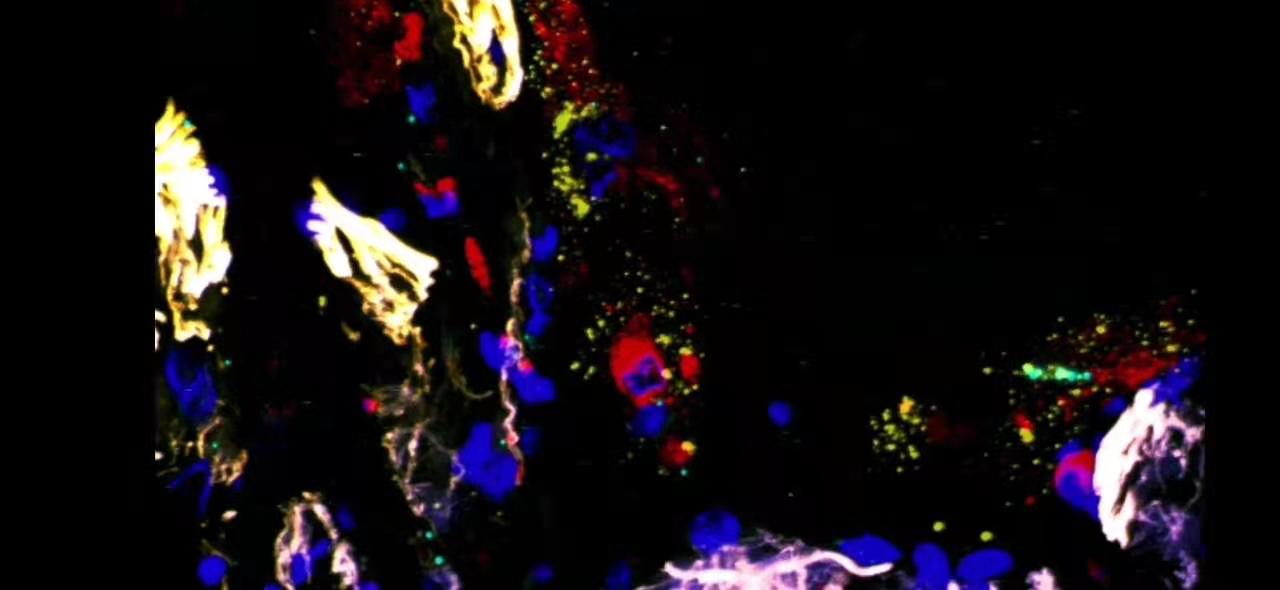

在CD206陽性肺泡巨噬細胞中檢測SARS-CoV-2陽性和陰性鏈轉(zhuǎn)錄產(chǎn)物。

結(jié)合免疫熒光顯微鏡檢查CD206(一種成熟的巨噬細胞(紅色))和smFISH(RNAscope)用于SARS-CoV-2陽性(黃色)和陰性(青色)轉(zhuǎn)錄產(chǎn)物。

大量和單細胞轉(zhuǎn)錄組譜分析表明,SARS-CoV-2感染了肺泡巨噬細胞,而巨噬細胞反過來又通過產(chǎn)生T細胞趨化因子做出反應。這些T細胞產(chǎn)生γ-干擾素以誘導肺泡巨噬細胞釋放炎性細胞因子,并進一步促進T細胞活化。具體過程如下圖所示。